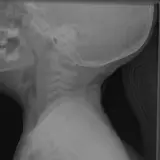

Over 2,100 interactive radiology cases, curated by radiologists for your level of training. Scroll, window, and view cases full screen โ€” just like on PACS. Click linked findings in each writeup to jump straight to them on the image. Cases include sample reports, a focused discussion section, original illustrations, and videos.

Casi completamente interattivi con gli strumenti che ti aspetti su un PACS: scroll, windowing, zoom, pan, misurazioni, ROI e modalitร  a schermo intero.

Annotazioni dettagliate evidenziano i reperti chiave direttamente sui casi. Clicca sui reperti collegati nella descrizione del caso per saltare alla loro esatta posizione sullo scan.